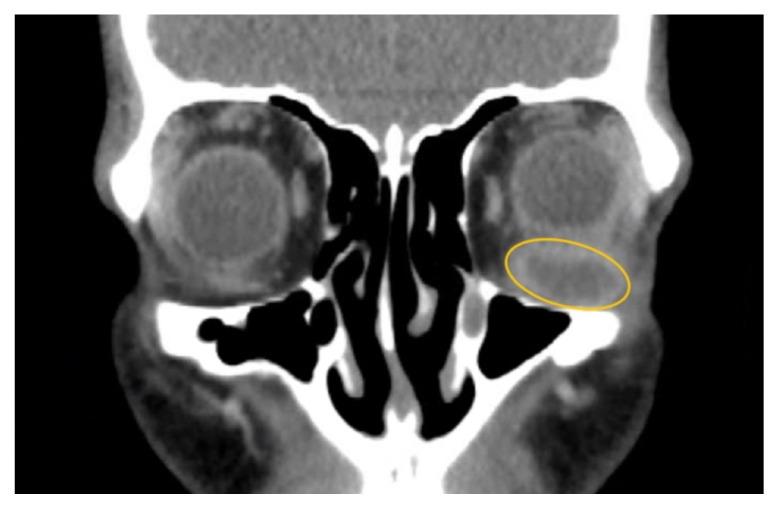

Soft tissue infections, including abscesses, are frequently encountered in the emergency department. However, abscesses of the inferior rectus muscle are rare and may present unique diagnostic and therapeutic challenges due to the scarcity of documented cases. This case report highlights the treatment of a 47-year-old male presenting with an abscess in the left inferior rectus muscle due to an acute Methicillin-resistant Staphylococcus aureus infection. Imaging revealed a distinct fluid collection compressing the left globe, causing restricted ocular motility and other symptoms. Despite prior intravenous antibiotics, the abscess persisted. While intravenous antibiotics are an important component of treatment, this case highlights the potential insufficiency of this approach alone, emphasizing a need for surgical intervention such as orbitotomy for drainage. This report contributes to the limited literature on inferior rectus muscle abscesses and underscores the need for further research and clinical attention to optimize patient outcomes.

软组织感染,包括脓肿,在急诊科很常见。然而,下直肌脓肿很少见,由于记录在案的病例稀缺,可能带来独特的诊断和治疗挑战。本病例报告重点介绍了一名47岁男性因急性耐甲氧西林金黄色葡萄球菌感染导致左眼下直肌脓肿的治疗情况。影像学检查显示有一个明显的液体积聚压迫左眼,导致眼球运动受限和其他症状。尽管之前使用了静脉抗生素治疗,但脓肿仍持续存在。虽然静脉抗生素是治疗的重要组成部分,但本病例突出了仅采用这种方法可能存在的不足,强调了手术干预(如眼眶切开引流)的必要性。本报告丰富了关于下直肌脓肿的有限文献,并强调需要进一步研究和临床关注以优化患者预后。